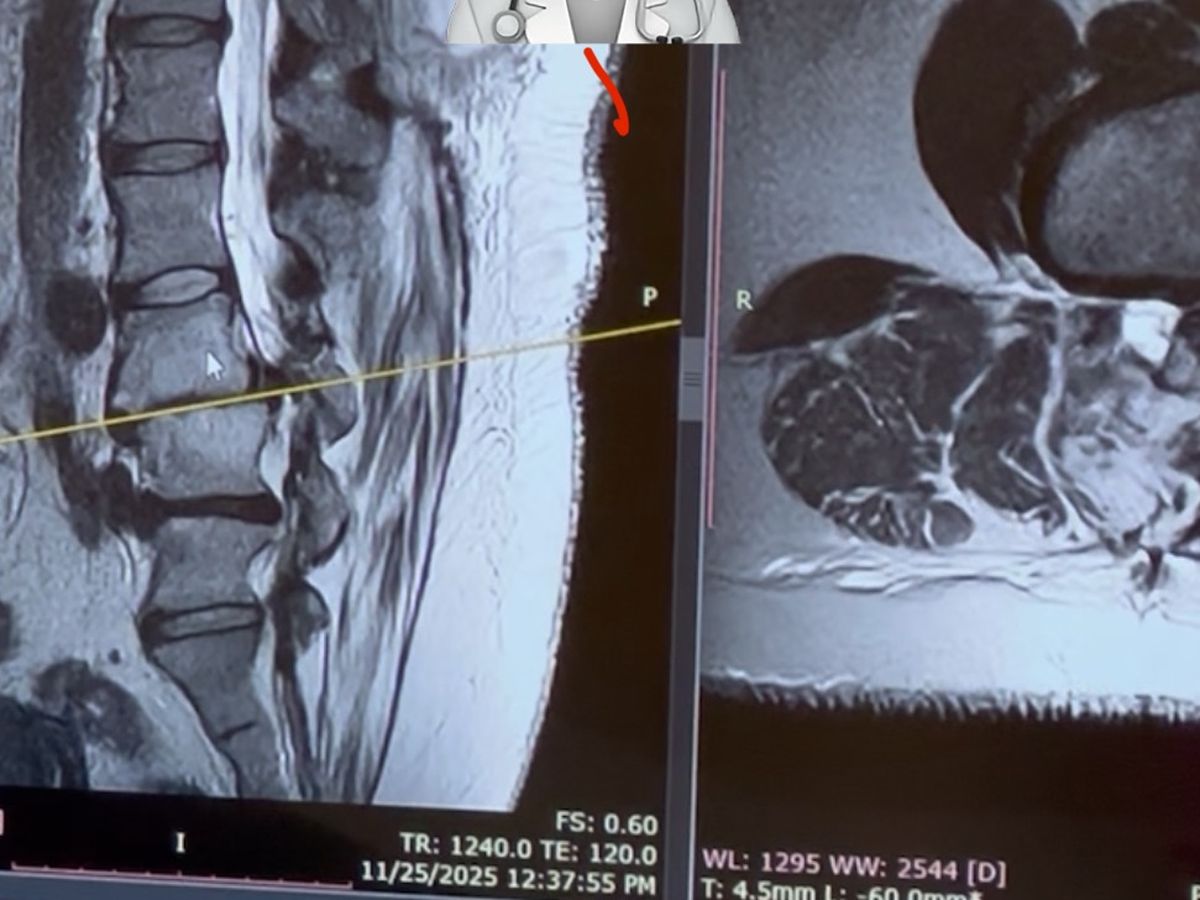

In the last few months, my condition has worsened to the point where, I can’t work, I can’t drive, I can barely stand long enough to cook or clean.I can’t even sit down long enough to do my daughter’s hair without severe pain.After months of struggling, doctor visits, and physical therapy 3x a week, I finally received the news I feared.

I need major back surgery.

It’s the only way for me to keep walking, keep caring for my family, and continue being the mom and daughter they need. The surgery requires 1 week in the hospital, 4–6 months of recovery at home, continued physical therapy afterward, and the heartbreaking reality that I won’t be able to work at all during this time.As the sole provider, this has put us in a frightening situation.